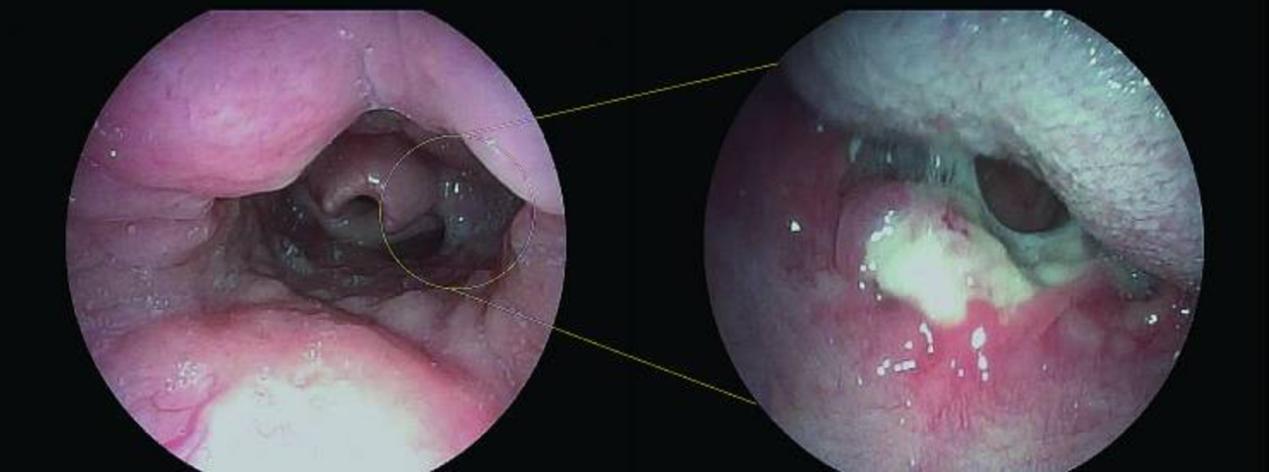

一名13岁女孩诉咽痛2个多月,伴有间歇性发热。入院前被当地医院诊断为化脓性扁桃体炎,并否认有抽搐或昏迷、恶心、呕吐或吞咽困难的病史。自发病以来,食欲和睡眠质量都很差。鼻咽镜检查显示咽部有一个溃疡病变肿块(图1)。增强计算机断层扫描(CT)显示悬雍垂轻微肿胀,双侧扁桃体增大(图2)。在没有手术禁忌症的情况下,获得父母的书面知情同意后,于全身麻醉下进行了扁桃体活检。

图1 鼻咽镜检查显示咽部有溃疡病变

图2 增强CT显示悬雍垂轻度肿胀,双侧扁桃体增大,左侧扁桃体点状钙化